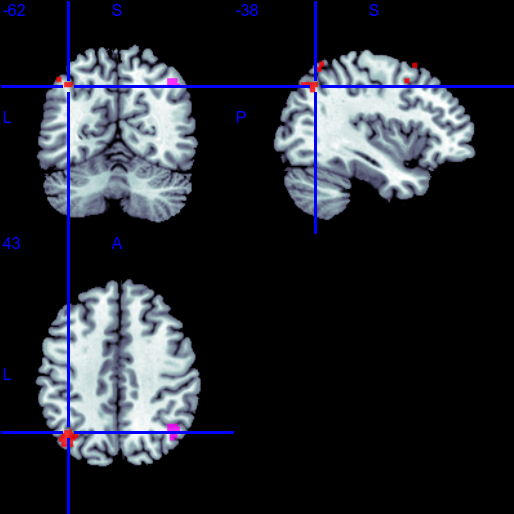

fMRI, Brain with Alzheimer's disease.